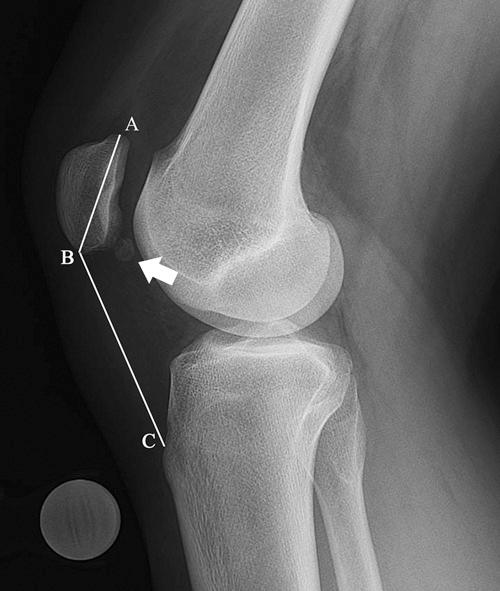

Although disorders of the patellofemoral joint are common in the athlete, their management can be challenging and require a thorough physical examination and radiologic evaluation, including advanced magnetic resonance imaging techniques.

Physical examination and imaging evaluation including standard radiographs are crucial in identifying evidence of malalignment or instability. Magnetic resonance imaging provides valuable information about concomitant soft tissue injuries to the medial stabilizers as well as injuries to the articular cartilage, including chondral shears and osteochondral fractures. Quantitative magnetic resonance imaging assessing the ultrastructure of cartilage has shown high correlation with histology and may be useful for timing surgery.

Evaluation of patellofemoral disorders is complex and requires a comprehensive assessment. Recent advancements in imaging have made possible a more precise evaluation of the individual anatomy of the patient, addressing issues of malalignment, instability, and underlying cartilage damage.